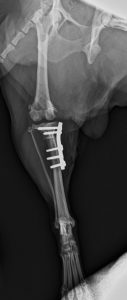

TPLO 2.0 Toy